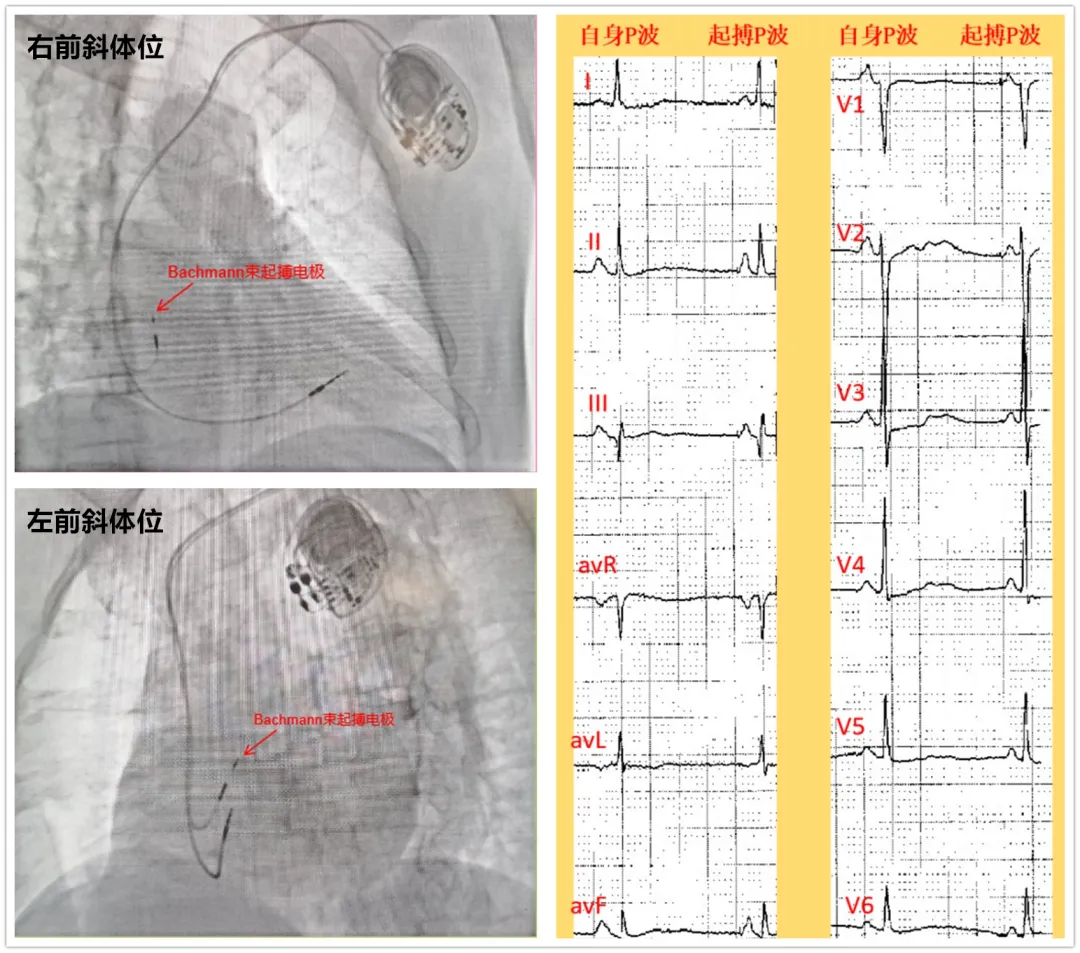

4月14日在刘现亮主任的指导下,阚晓红主任医师、宋洪勇副主任医师为患者实施双腔起搏治疗,从左侧腋静脉穿刺,到心房Bachmann传导束电极植入、右心室间隔部电极植入,至最终完成起搏器植入,用时1小时。心电图P波宽度由术前130ms缩窄为100ms,达到双心房同步激动、起搏,复查动态心电图房颤消失。患者术后恢复情况良好,于4月24日出院。

据接诊的阚晓红主任医师介绍:根据患者症状,以及动态心电图检查提示房颤合并长间歇,入院后心电图检查提示窦性心动过缓、窦性停搏、短阵房速、阵发性房颤伴有长间歇,诊断为病态窦房结综合征(病窦),这是一种能让人晕厥、甚至心衰、猝死的疾病,患者出现的头晕、黑曚、一过性意识丧失症状都与“病窦”相关,这类患者的最佳治疗方法是植入永久性心脏起搏器。但考虑到常规的起搏器是与正常人体心脏起搏的顺序不同的,因此虽然解决了心率慢的问题,却不能减少房颤的发生,更可能增加心衰的风险。结合患者病情,心血管内二科刘现亮主任带领团队决定为患者实施心房Bachmann传导束起搏手术。该术式是将起搏电极放置于房间隔上部即Bachmann传导束区域进行起搏,可以更接近左、右心房的同步激动,接近正常人体的心脏起搏顺序。同步的双心房激动可改善心房的血流动力学,有助于维持有效的心房收缩和心室充盈。更为重要的是,Bachmann传导束区域的同步起搏有望降低阵发性房颤的发生率,预防因心房不同步导致的心律失常和心功能不良。